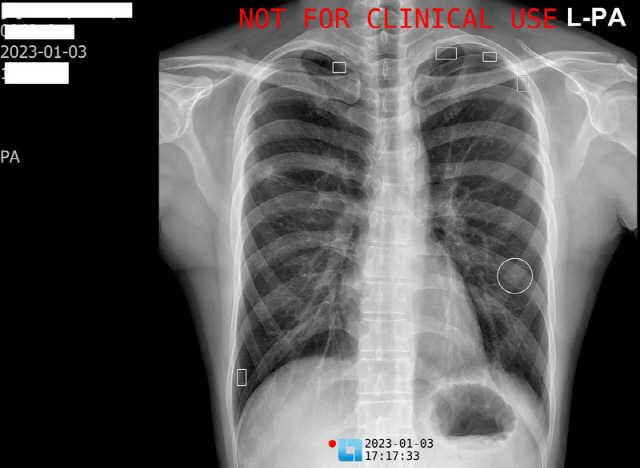

하나이비인후과병원이 인공지능을 이용한 흉부 X-ray 영상 분석 시스템을 도입, 가동에 들어갔다.

하나이비인후과병원은 LuCas-CXR을 이용해 환자들의 기관지와 폐 관련 질환을 보다 빠르고 정확하게 진단해 더욱 효과적인 치료를 할 수 있을 것으로 기대하고 있다.

LuCas-CXR 도입은 건양대학교병원 김종엽 교수(건양대 의대 헬스케어 데이터사이언스 센터장)팀이 진행하는 '수요자 맞춤형 의료인공지능 임상실증 연구지원센터 사업'의 일환으로 추진된 것이다.